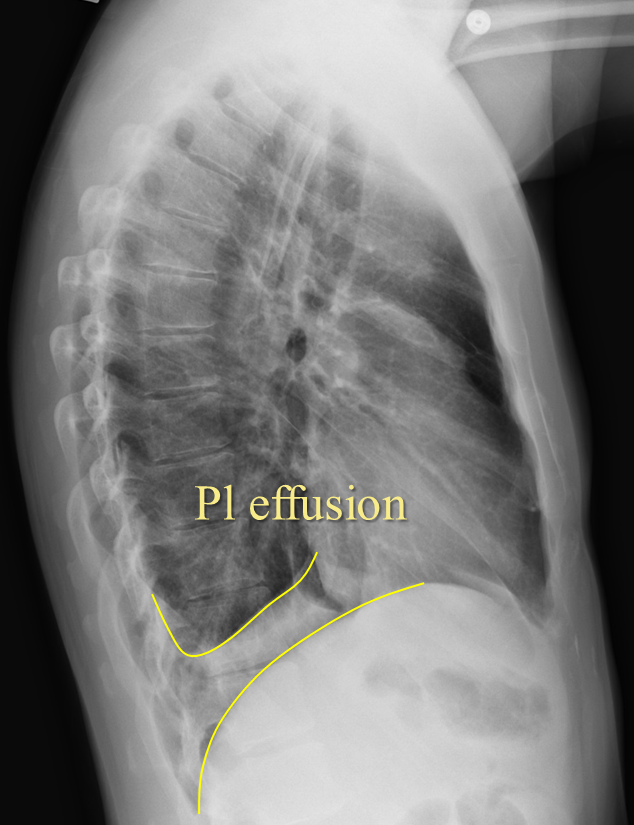

Pleural Effusion X Ray Lateral Chest X Ray View For Pleural Effusion Ngt, ett, right sided picc and left cvl are in appropriate position. At first glance there is clearly white out of the left hemithorax, with a meniscus sign. — effusion and collapse. Pleural effusions are collections of fluid. A homogenous opacification is noted in the right lower zone with the opacity seen to track along the lateral chest wall.. Chest X Ray View For Pleural Effusion.